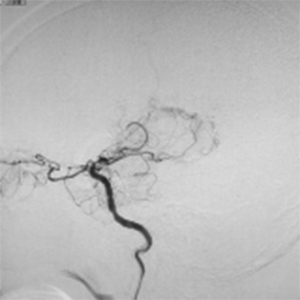

バイパス術で増加した脳血管